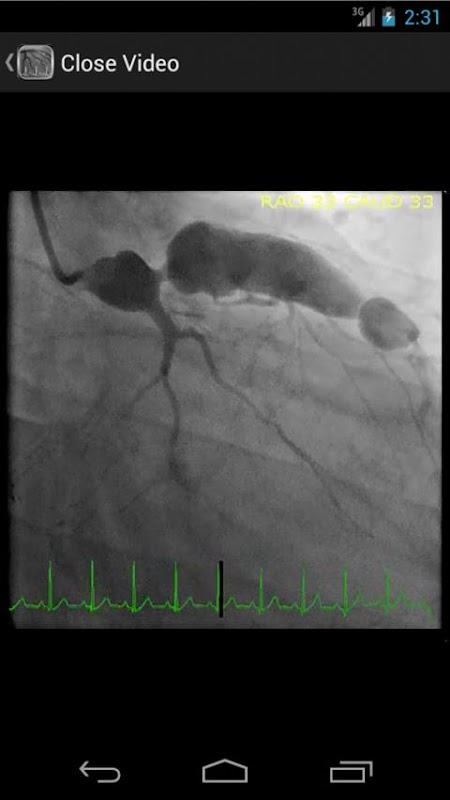

* Doorzoekbare database met meer dan 30 video's (coronaire angiografie, ventriculograms en aortograms) van zowel gemeenschappelijke als zeldzame bevindingen in het hartcatheteriserenlaboratorium